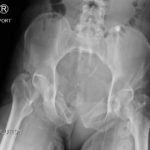

The initial radiograph of the pelvis shows an open-book pelvic fracture deformity with pubic symphyseal dislocation, left greater than right sacroiliac diastases, and fractures of the left superior and inferior pubic rami, right inferior pubic ramus, and left acetabular anterior column. The additional inlet and outlet radiographs of the pelvis after application of a pelvic binder also show an open book fracture with significant improvement of the widened pubic symphysis.